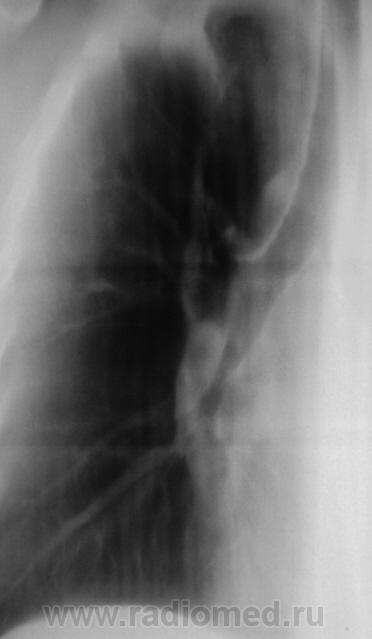

Боковая проекция.